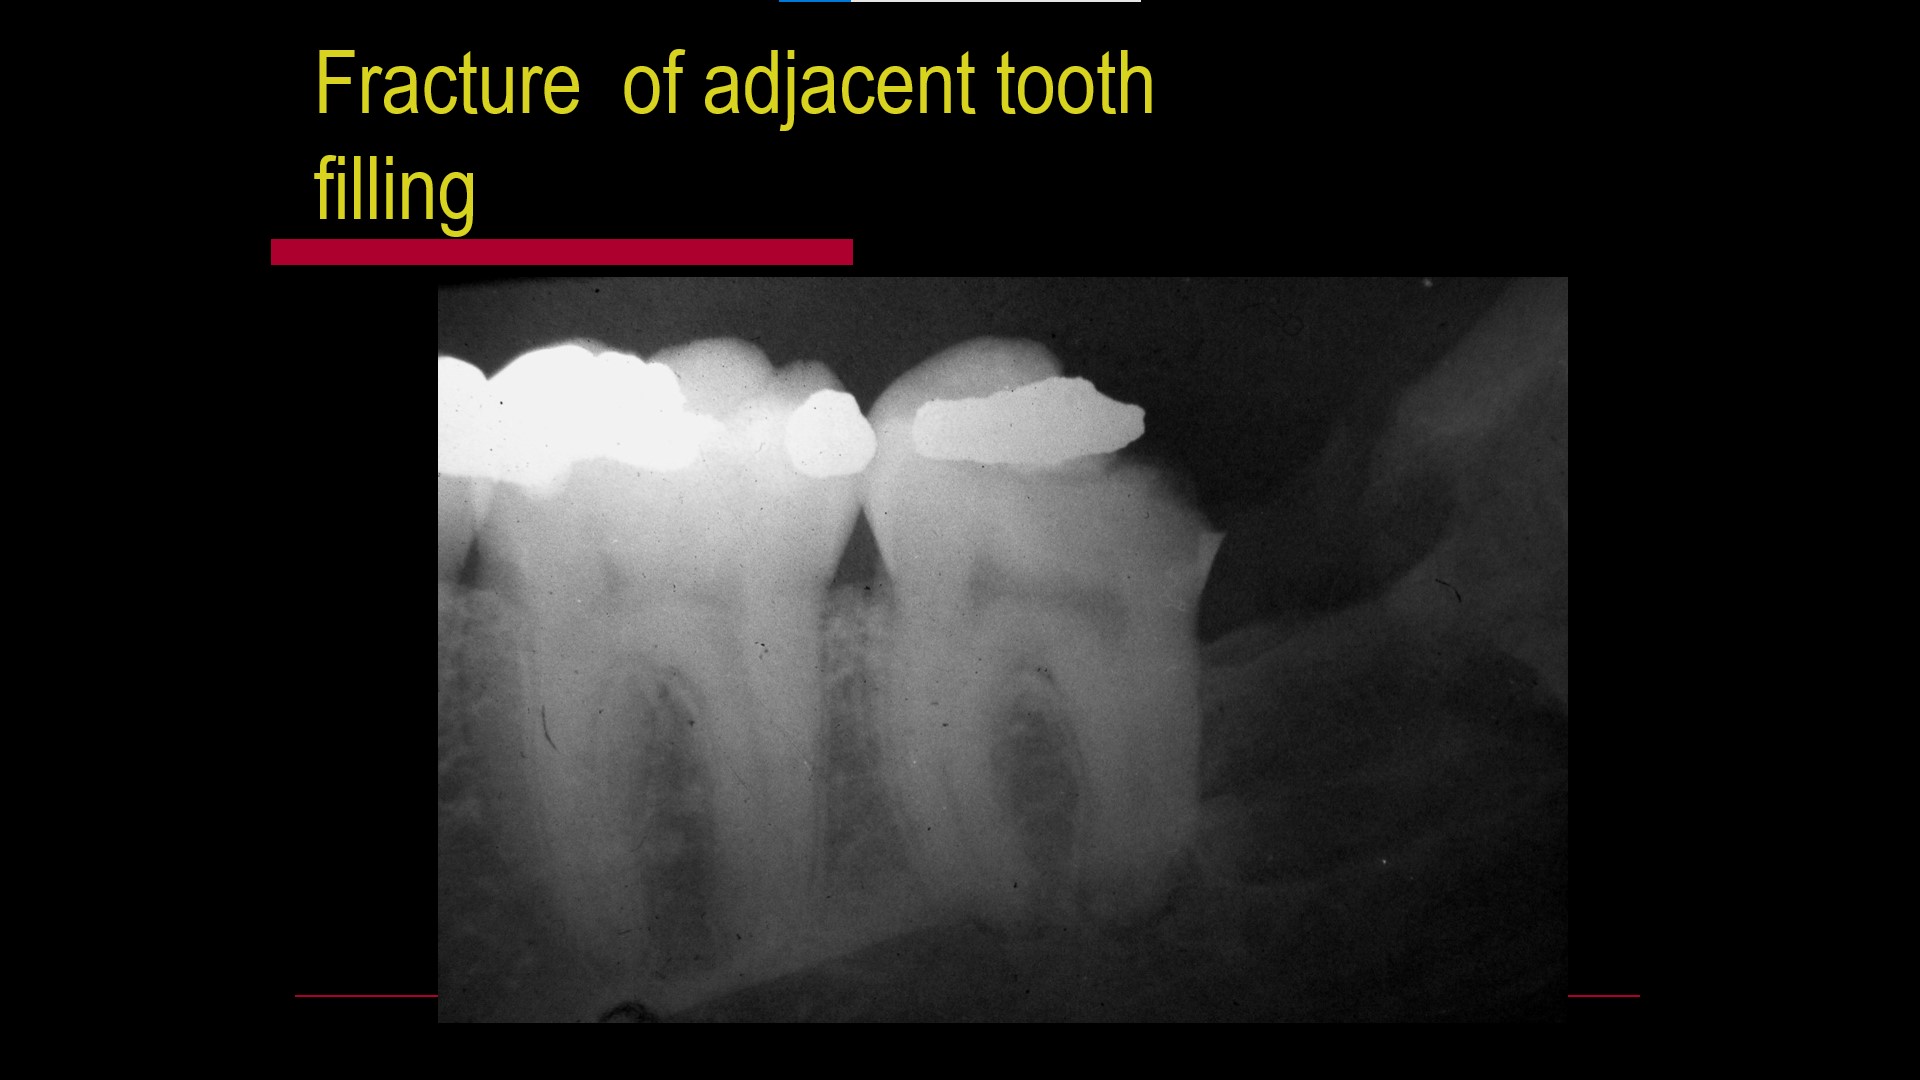

Impacted teeth